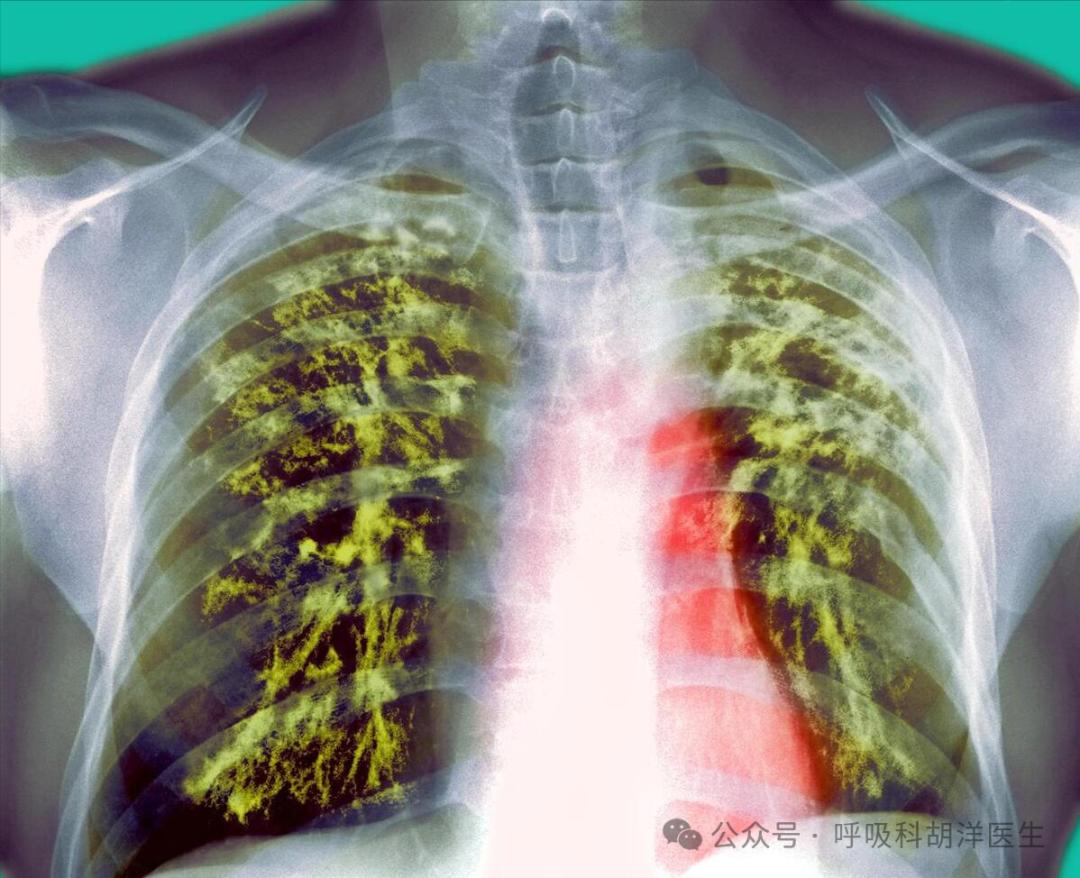

细菌耐药性已成为未来十年最棘手的医疗问题。非常耐药的细菌可能会让患者在无药可用的情况下逐渐失去生命。下呼吸道感染已经成为人类死亡的第三个主要原因,包括非常耐药的细菌,结核细菌也是如此。有些耐药结核患者没有合适的药物,只能看到病情逐渐恶化。

如今,新的曙光已经照进了这些患者的生命。超短程药物计划使耐药结核的治愈再次成为现实,这主要是由于药物贝达喹啉和普托马尼的出现。这两种药物在耐药结核的治疗中发挥着重要作用,原本无法消除的结核再次得到抑制甚至消除。这两种药物可以有效消除耐药结核,同时使用另外两种抗药结核抗生素-利奈唑胺和莫西沙星。此外,近两年的传统计划将疗程缩短至六个月,不但疗效准确,病人能很好地完成疗程,可说是近几年结核治疗领域最大的突破。